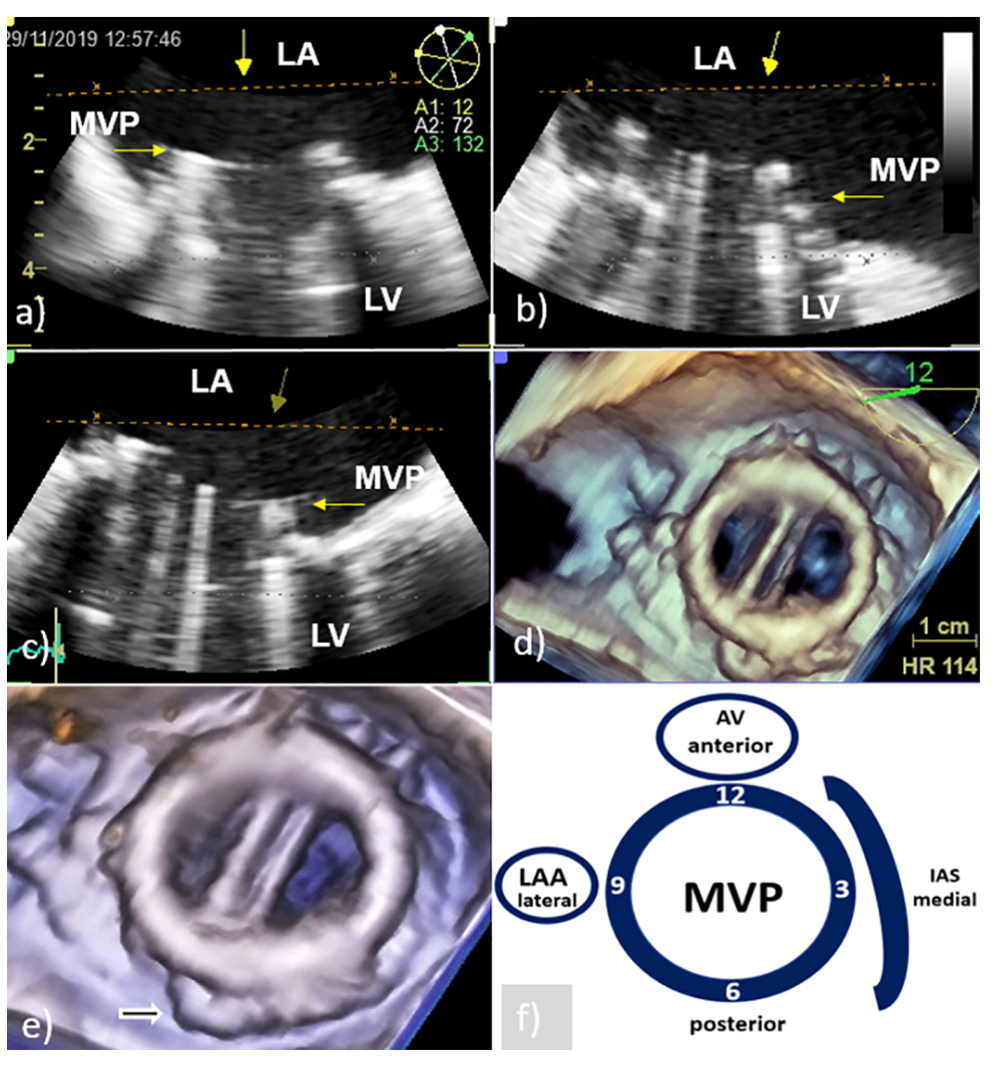

According to recent reports, 3D TEE provides clear, rapid, and detailed anatomical visualization of mechanical and bioprosthetic mitral valves in real time ensuring better assessment of mitral PVE-related complications and significant improvement in monitoring and preoperative surgical planning [9,10,11,12,13,14]. The surgeon’s view, which shows the mitral prosthesis with the aortic root at the 12 o’clock position, is identical to what the surgeon sees and is recommended as a standard orientation (Figure 1) [9,13]. Therefore, 3D TEE precise anatomical imaging of the mitral valve is better understood by cardiac surgeons [8]. An additional advantage of 3D TEE is better visualization of the mitral prosthesis from the left ventricle, although shading caused by a mechanical prosthesis can sometimes make its clear visualization difficult or impossible [8]. Finally, 3D TEE echocardiographic modality is capable of improving communication between members of the IE team.

Perivalvular abscess is more often associated with PVE of the aortic valve than with mitral PVE and is thought to be present when a specific area of reduced echo density is found on the echocardiogram or when echolucent cavities are found within the valvular ring or myocardial structures surrounding the valvular infection [7]. In case of mitral PV, the spread of infection to perivalvular tissue is more often manifested as new or increased paravalvular regurgitation (Figure 4) or valve dehiscence (Figure 5) [4]. New regurgitation in patients with IE of bioprosthesis detected several years after valve replacement is primarily caused by perforation or rupture of the leaflets with consequent varying degrees of insufficiency and only rarely by paravalvular mechanisms [4,17].

Although 2D TEE is a useful diagnostic tool in detection of paravalvular complications (sensitivity 90% and specificity 90%), 3D TEE provides anatomical imaging that can better identify location, number, shape, and size of damage [1,13]. Recent studies with 3D TEE found that mitral PV dehiscence is most frequently located in the posterior and lateral part of mitral annular region [1,13]. In relation to the extent of the affected PV ring, the size of the defect can be classified into three categories: mild (<10%), moderate (10–29%) and severe (>30%) [13]. If the PV dehiscence exceeds 40% of the valve ring, rocking the prosthesis can cause severe regurgitation and precipitate congestive heart failure. In addition, when assessing significance of a defect, its shape and surface should be taken into account [13]. Namely, a circular defect with a fairly large surface area occupying less than 10% of the ring circumference may be hemodynamically more significant than a slit-shaped defect with a small surface area occupying more than 20% of the circumference (Figure 4).

Figure 4. Transesophageal echocardiography of MVP endocarditis caused by Streptococcus bovis. Two-dimensional TEE shoved localized dehiscence of the MVP with a paravalvular leakage (white arrow) (a,b); surgeon’s view of MVP with suspected dehiscence (white arrow) in the lateral (8–9 o’clock) position (c); enlarged and rotated 3D TEE image from different angle confirms a defect (white arrow) with fairly large surface area that occupies approximately 15% of the MVP circumference and causes hemodynamically significant regurgitation (d). 2D TEE—two-dimensional transesophageal echocardiography; 3D TEE—three-dimensional transesophageal echocardiography; MVP—mitral valve prosthesis; LA—left atrium; and LV—left ventricle.

Figure 5. Transesophageal echocardiography of the mitral valve 15 days after surgical correction due to mitral valve prolapse. Two-dimensional TEE revealed dehiscence of the C-E ring with consequent severe regurgitation (white arrow, a,b); 3D TEE showed almost complete dehiscence of the C-E ring which was attached to the native ring only on the smaller posterolateral segment (white arrow); the asterisk indicates the surface of the native mitral orifice (c—in systole, d—in diastole). Clinical and laboratory parameters along with Staphylococcus epidermidis revealed in blood culture suggest that dehiscence was caused by infective endocarditis. 2D TEE—two-dimensional transesophageal echocardiography; 3D TEE—three-dimensional transesophageal echocardiography; C-E—Carpentier-Edwards ring; LA—left atrium; and LV—left ventricle.